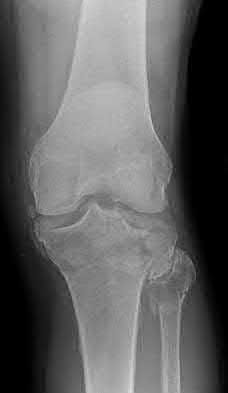

1. # A 32-year-old male sustains the injury shown in Figure A and undergoes treatment as shown in Figure B. Following placement of this implant, what is the best technique to confirm it is not too proud proximally?

1. Lateral radiograph of the knee

2. AP radiograph of the knee

3. Oblique radiographs of the knee

4. Merchant radiograph of the knee

5. Internally rotated 45 degree view of the knee Corrent answer: 1

The safe zone for tibial nail placement as seen on radiographs is just medial to the lateral tibial spine on the anteroposterior radiograph and immediately adjacent and anterior to the articular surface as visualized on the lateral radiograph.

Tornetta et al specifically located the safe zone for nail entry in a study using fresh frozen cadaver knees. The authors found that the safe zone for nail placement is located 9.1+/-5 millimeters lateral to the midline of the plateau and three millimeters lateral to the center of the tibial tubercle. The width of the safe zone averaged 22.9 millimeters and was as narrow as 12.6 millimeters.

The starting point of the of the nail can be best viewed on the lateral knee radiograph, an example of which is shown in Illustration A. Illustration B shows the "sweet spot" for nail insertion as defined by Tornetta.